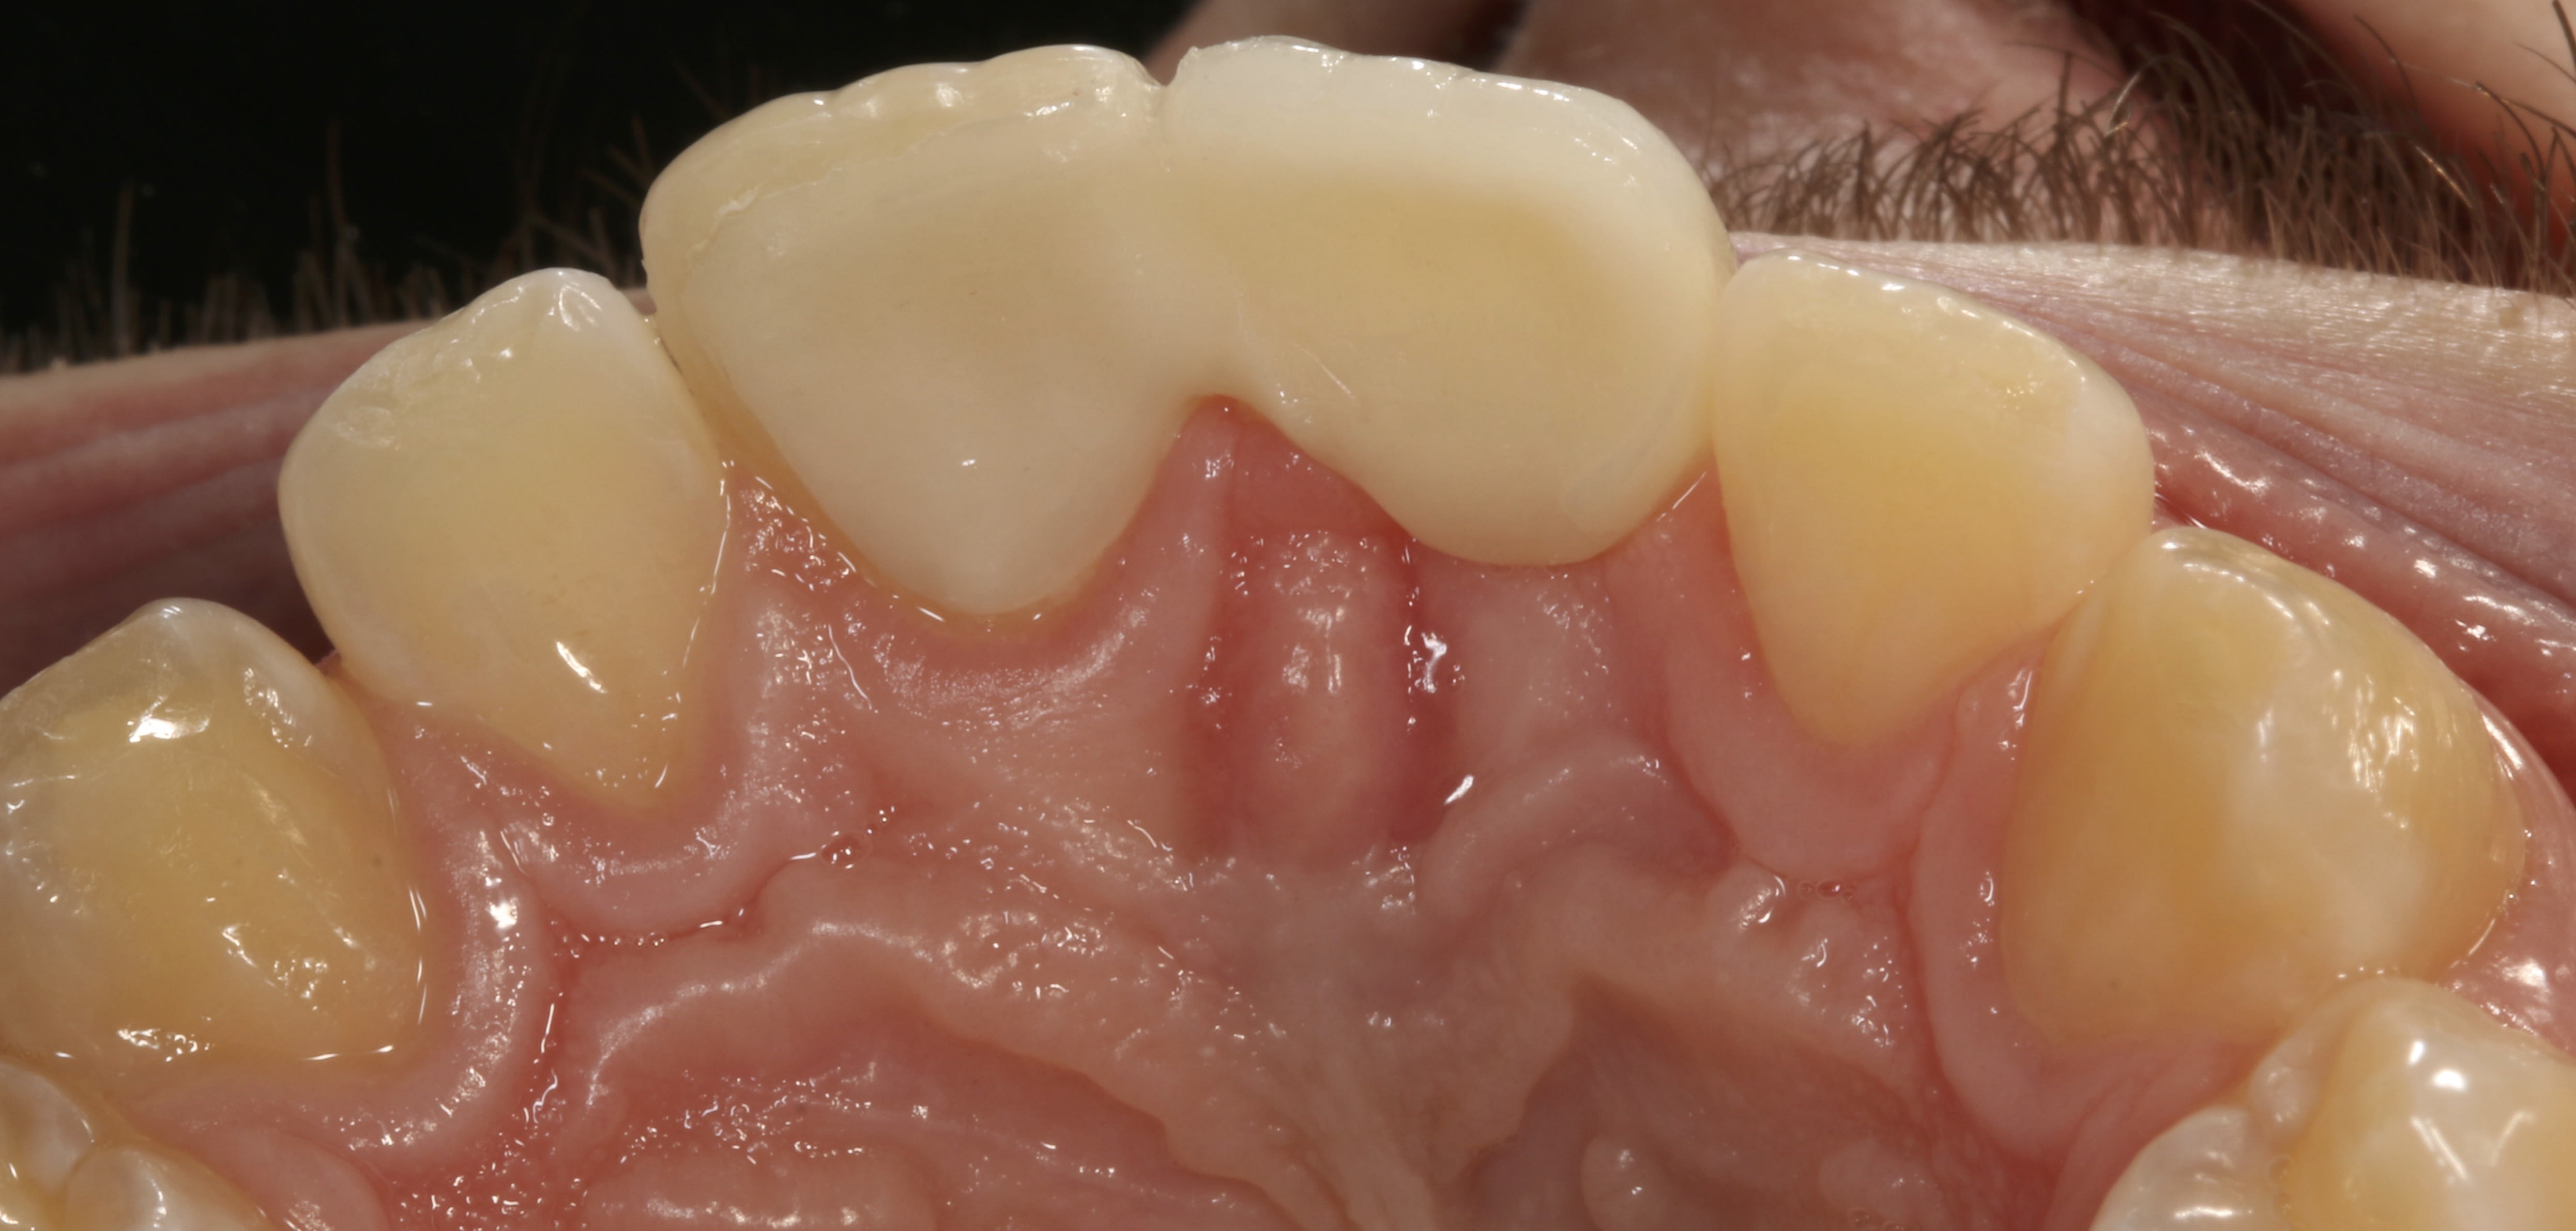

Une autre image du cas en palatin avec un axe un peu décalé montre mieux les crêtes marginales mésiales...l'idée est de concentrer l'occlusion sur les crêtes marginales de la 21, car effectivement il y a risque de migration de cette dent suite à la perte importante d'os vestibulaire liée à la résorption externe de la 11 . Et c'est pour cela que la crête marginale distille de la 21 n'est pas incluse dans la taille, elle peut alors conserver son guidage originel, est orienter ainsi le travail prothétique.